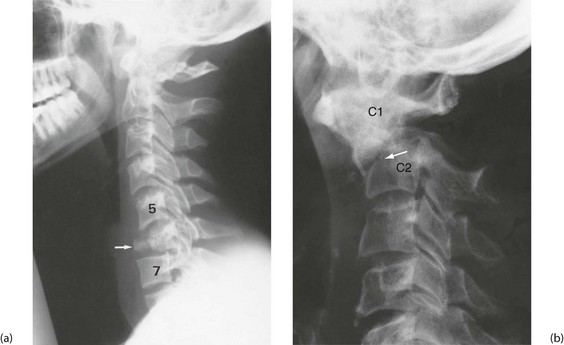

X-rays and other investigations: In major trauma, the cervical spine (see below, Fig. 15.10), chest and pelvis are X-rayed in the resuscitation room. The chest films must be good enough to exclude major chest wall, mediastinal and lung injuries and provide a baseline if the patient later deteriorates. Polytrauma patients, or patients with serious head injury should have rapid assessment and stabilisation before swift transfer for trauma CT scan. Patients should not be moved to the CT scanner until they are stable—the machine is known as the ‘donut of death’ in ATLS parlance.

Spinal fractures (Fig. 15.10): These may be pathological or not. The most common pathological fracture is a fragility (crush) fracture in osteoporotic bone, typically in lumbar spine bodies in older patients. Up to 90% of patients in their 80s are believed to have sustained a vertebral fragility crush fracture. These cause pain and disability but do not benefit from surgical treatment and take time to settle. Pathological fractures through metastatic deposits are a common new presentation of a known neoplasm or of an undiagnosed primary.

Non-pathological spinal fractures usually occur with high energy trauma, but vertebrae can be crushed in healthy adults after a vertical fall from standing height. Any patient suffering sufficient trauma should be assumed to have a spinal injury until proven otherwise. Most attention is directed to the vulnerable cervical spine (see below), but the entire spinal column should be assessed.

A cervical spine CT scan should be performed (usually with a CT head) if the criteria are not met. Thoracolumbar spine imaging is indicated if there is pain, bruising, swelling, deformity or abnormal neurological signs attributable to the region. A fracture anywhere in the spine is an indication for full spinal imaging. Unconscious patients cannot be assessed clinically and require radiological clearance of the whole spine (i.e. exclusion of injuries). If in doubt, spinal immobilisation devices are left in place, logrolling for movement and high frequency nursing care is continued while seeking detail about the fracture.